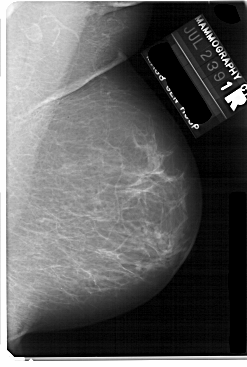

A_1738_1.LEFT_MLO

LEFT_MLO LINES 5491 PIXELS_PER_LINE 3511 BITS_PER_PIXEL 12 RESOLUTION 43.5 OVERLAY

FILE: A_1738_1.LEFT_MLO.OVERLAY

TOTAL_ABNORMALITIES 1

ABNORMALITY 1

LESION_TYPE MASS SHAPE LOBULATED MARGINS ILL_DEFINED

ASSESSMENT 4

SUBTLETY 2

PATHOLOGY BENIGN

TOTAL_OUTLINES 1

BOUNDARY